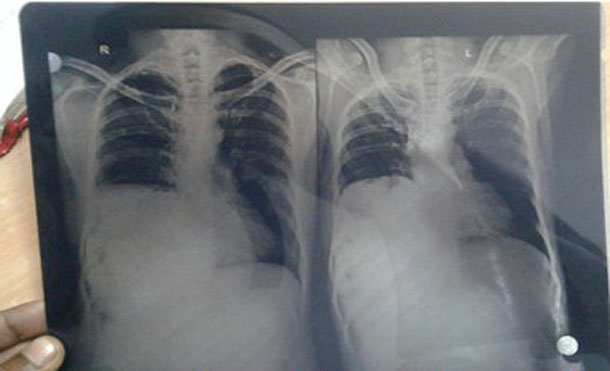

महिषामुंडा कहलगांव के रहने वाले मो. शफीक को सर्दी-खांसी थी। आर्थिक रूप से कमजोर शफीक इलाज के लिए मेडिकल कॉलेज अस्पताल के ओपीडी में पहुंचा था। लगभग एक सप्ताह तक दवा खाने के बाद भी आराम नहीं मिला तो मरीज को एक्स-रे के लिए भेजा गया। एक्स-रे में छाती की दायीं ओर काफी विषमता दिखी।

एक्स-रे की रिपोर्ट देखने के दौरान रेडियोलॉजिस्ट डा. प्रसून कुमार की जिज्ञासा बढ़ गई। उन्होंने इस केस पर विभागाध्यक्ष डॉ. एके मुरारका और डॉ. मुकेश बिहारी से विमर्श किया। विभागाध्यक्ष भी रिपोर्ट देख चौंक गए और बिना एडवाइस मरीज का नि:शुल्क अल्ट्रासाउंड और सिटी स्कैन कर आंतरिक बनावट को जानने का प्रयास किया।

दोनों जांच में स्पष्ट हुआ कि मरीज की दायीं किडनी, आंत और लीवर छाती में हैं। इसके बाद मेडिसिन विभाग के वरिष्ठ चिकित्सक डा. विनय कुमार के साथ डॉक्टरों ने मशविरा कर मरीज को किसी रिसर्च सेन्टर में रेफर करने का निर्णय लिया है।

दायें फेफड़े में है सिकुड़न

रेडियोलॉजी के विभागाध्यक्ष डॉ. एके मुरारका ने कहा कि मैंने अपने कॅरियर में इस तरह का केस नहीं देखा है। मरीज अभी सामान्य जीवन जी रहा है लेकिन दायें फेफड़े में इसकी वजह से सिकुड़न है। रिसर्च सेन्टर में ऐसे केस के समाधान का प्रयास होता है।